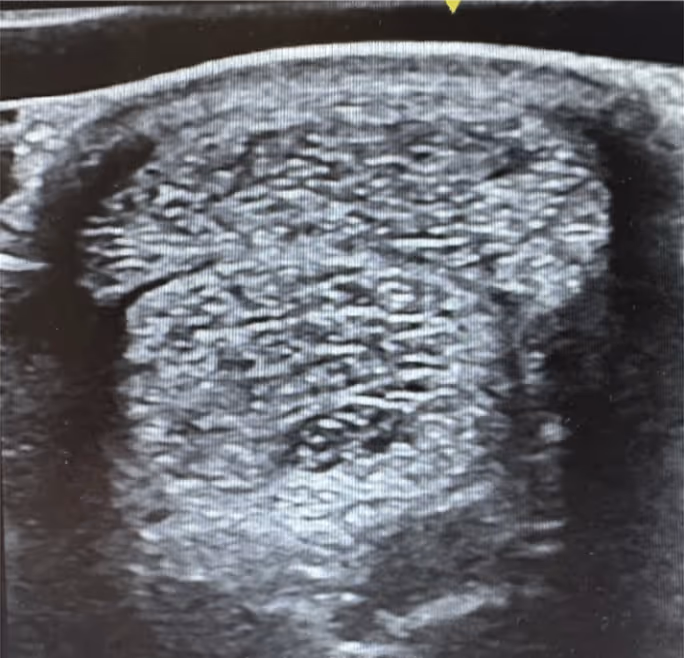

The model organism used is an elastase enzyme-treated rat. The enzyme damages a significant number of lung air sacs (alveoli) mimicking the case of lung emphysema in patients.

Testing the effect of SMS cells instilled into the lung of this rat resulted in a high percentage of alveoli regeneration using a mere single dose of SMS cells. Different regimens are currently being studied to optimize the healing effect of these cells.